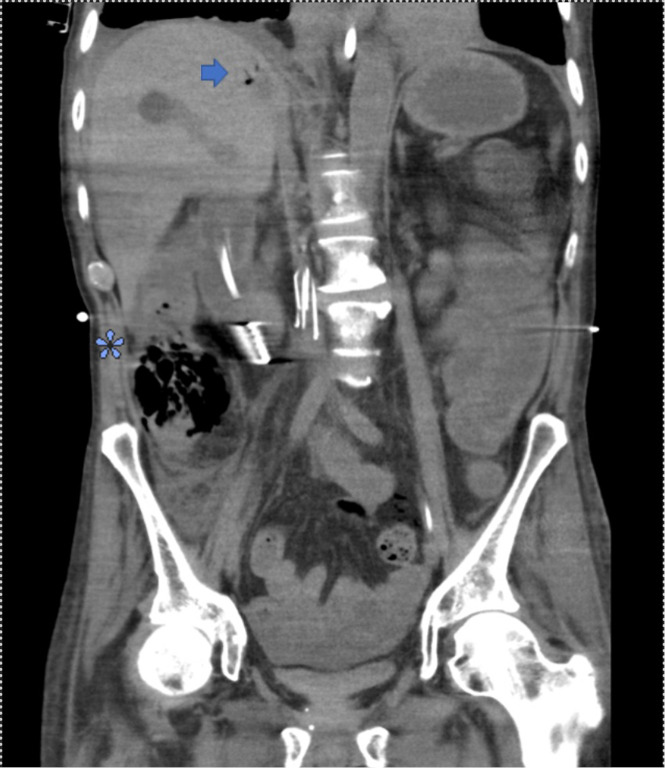

Case description: We present herein the first reported case of peritonitis secondary to jejunal and cecal perforation secondary to angio-IA after lung transplantation (LT) in a 62-year-old male. The patient was admitted to the hospital for acute cellular rejection requiring high-dose immunosuppression. His course was complicated by respiratory failure secondary to IA, with resulting multiorgan system dysfunction during which time peritonitis was noted on examination and cross-sectional imaging demonstrated pneumatosis, portal venous gas, and pneumoperitoneum. The patient required emergent surgical intervention and underwent an exploratory laparotomy, jejunal resection, right hemicolectomy, and end ileostomy with colonic mucus fistula. Final pathologic analysis of resected specimens demonstrated angio-IA in both the jejunal and cecal segments with associated transmural ischemic necrosis.